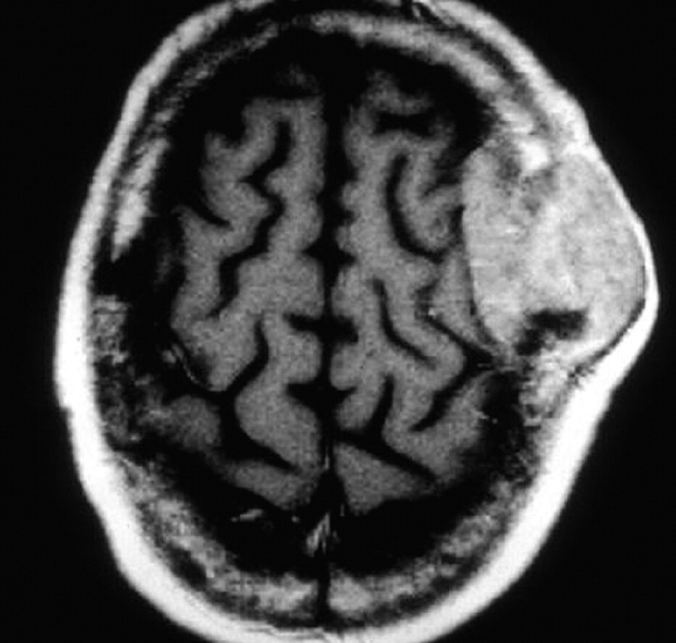

Advanced HIV infection can lead to opportunistic infections of the brain and spinal cord. Well-known pathogens include Toxoplasma gondii, Cryptococcus neoformans, and JC virus. Primary central nervous system lymphoma may also affect severely immunocompromised patients. Infections and malignancy cause variable neurologic symptoms, usually reflecting the location and severity of disease.

For example, patients with solitary lesions often present with headache or focal deficits, whereas patients with increased intracranial pressure from substantial masses (with or without edema) may have visual disturbances, nausea, or altered consciousness. Patients with meningitis or encephalitis generally present with one or more of the following: fever, headache, neck pain or stiffness, altered mental status, or seizure. Symptoms of myelopathy include weakness and sensory changes; upper motor neuron signs, such as spasticity and hyperreflexia, may also be found.

Head computed tomography showing a space-occupying, solitary lesion in a patient with primary central nervous system lymphoma.